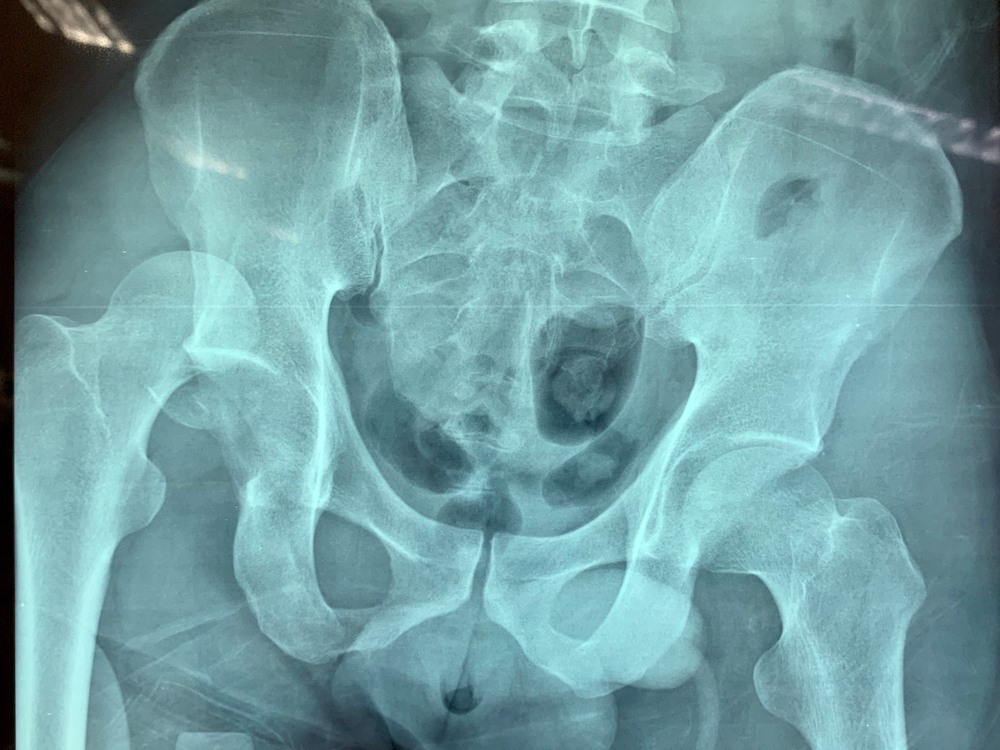

L’articolazione dell’anca, una delle più importanti e mobili del nostro corpo (è quella che ci permette di camminare), è costituita dal femore (l’osso della coscia) e dall’osso iliaco (che fa parte del bacino). L’estremità prossimale del femore (detta testa del femore), di forma convessa, trova alloggio in una cavità dell’osso iliaco, detta acetabolo.

Quando, a causa di un evento traumatico, la testa del femore fuoriesce dall’acetabolo, cioè dal suo alloggio naturale, si avrà una lussazione dell’anca, evento estremamente doloroso e invalidante.

La lussazione dell’anca può essere incompleta, quando il contatto fra le ossa che costituiscono l’articolazione viene in parte conservato, o completa, quando il contatto fra le ossa viene a mancare completamente.

Nella stragrande maggioranza dei casi, questo tipo di infortuni causa una lussazione posteriore: in pratica la testa del femore fuoriesce dall’acetabolo portandosi indietro e leggermente in alto rispetto a quest’ultimo. Purtroppo, non di rado questo infortunio è accompagnato dalla frattura dell’acetabolo e/o della testa del femore.

La diagnosi di lussazione d’anca è piuttosto semplice: si basa su un esame obiettivo, sui sintomi del paziente e su test radiologici che, oltre a confermare la presenza della lussazione, servono a escludere danni più gravi come fratture, osteonecrosi (morte del tessuto osseo dovuto al ridotto apporto di sangue) e lesioni a tendini, muscoli e legamenti.